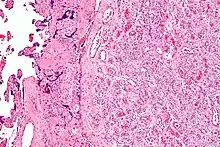

| Micrograph of a chorangioma. H&E stain. | |